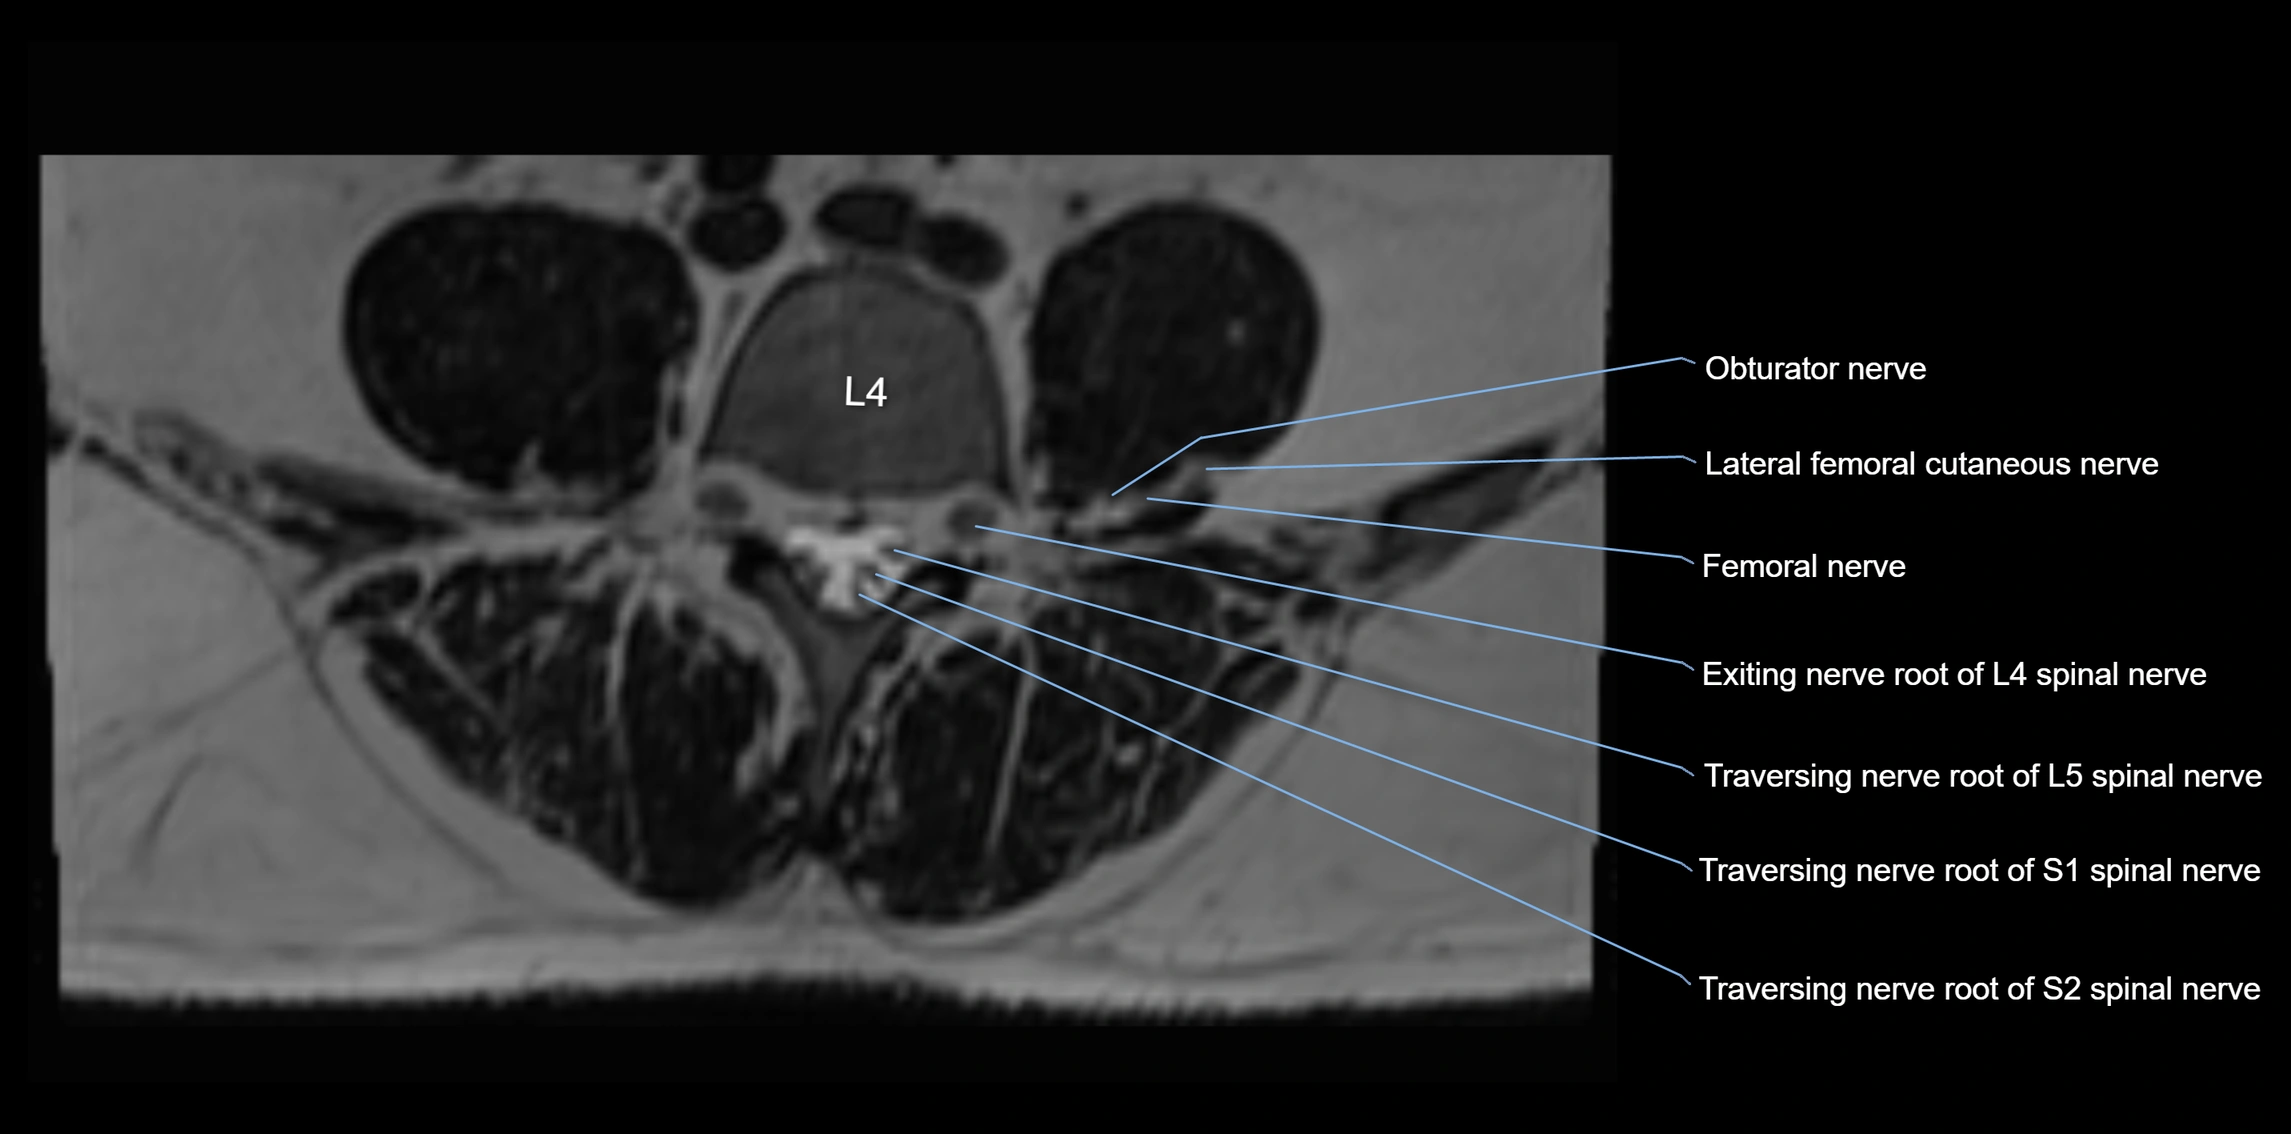

MRI image

image